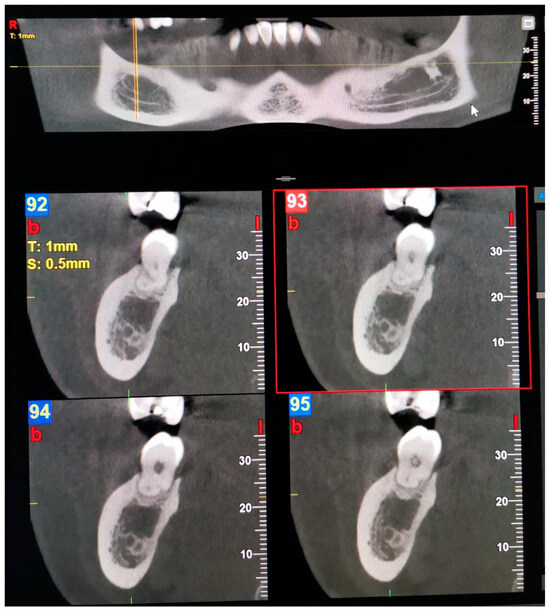

Examples of images considered positive for BMC and TMC are shown in Figure 1, Figure 2, Figure 3, Figure 4, Figure 5, Figure 6 and Figure 7. Regarding the distribution among patients, 36 subjects (15.13%) showed at least one BMC, 12 (5.04%) bilaterally, while 2 subjects (0.84%) showed a TMC. Among patients with cases considered positive for BMC, 21 were women, accounting for 8.82% of the total studied population and 14.89% of female patients overall. On the other hand, 15 BMC patients were men, accounting for 6.30% of the whole sample and 15.4% of men in the study. Considering the hemi-mandibles, BMC appeared in 9.87% of images, while TMC only appeared in 0.42%. The Patient group that was positive for BMCs had a mean age of 34 ± 13.30, while the group that was positive for TMCs presented a mean age of 43 ± 19.8. Pearson’s Chi-Square test was not significant; no association was found between gender and the prevalence of mandibular canals.

Figure 5. Panoramic view and transverse section of a right Type 4—Buccolingual BMC. l, lingual. b, buccal. T, thickness. S, section.